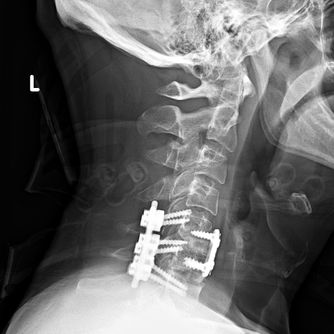

Life Is The Greatest Gift You Can Give. It can also be the greatest gift you receive. I know because I received this gift. I had a catastrophic injury to my cervical spine and donor bone is the reason I can walk and talk today. Without the Gift of Life, I would have been a quadriplegic on a ventilator. My name is Joe Rothpearl. I am a donor recipient and a Proud Partner with Donate Life New York State (Click to Register Here!!!)

I am the beneficiary of two donor bones from my first two surgeries in 2012. I am forever aware of the two selfless donors who gave me the chance to continue living my life. I feel it is my duty to stand for them as well as myself - with the gift of standing, walking and talking that they gave me!!! I also use three exclamation points a lot hoping people will ask me 'why?'. It's one for each of the people whose bones are a part of me now. I live for all three of us now. Coincidentally I have three Instagram Pages and three Facebook pages. I also post daily on Twitter, Pinterest. and frequently on YouTube, LinkedIn, and Google. I've been featured by Chrysler’s Mopar Magazine, MTF Biologics and Good Morning Rochester/13WHAM News. I am very excited to be a Donate Life Partner and appreciate every opportunity to help others smile. Read more about Challenger Joe, connect with me on social media and Please Help Me Share This Message!!!